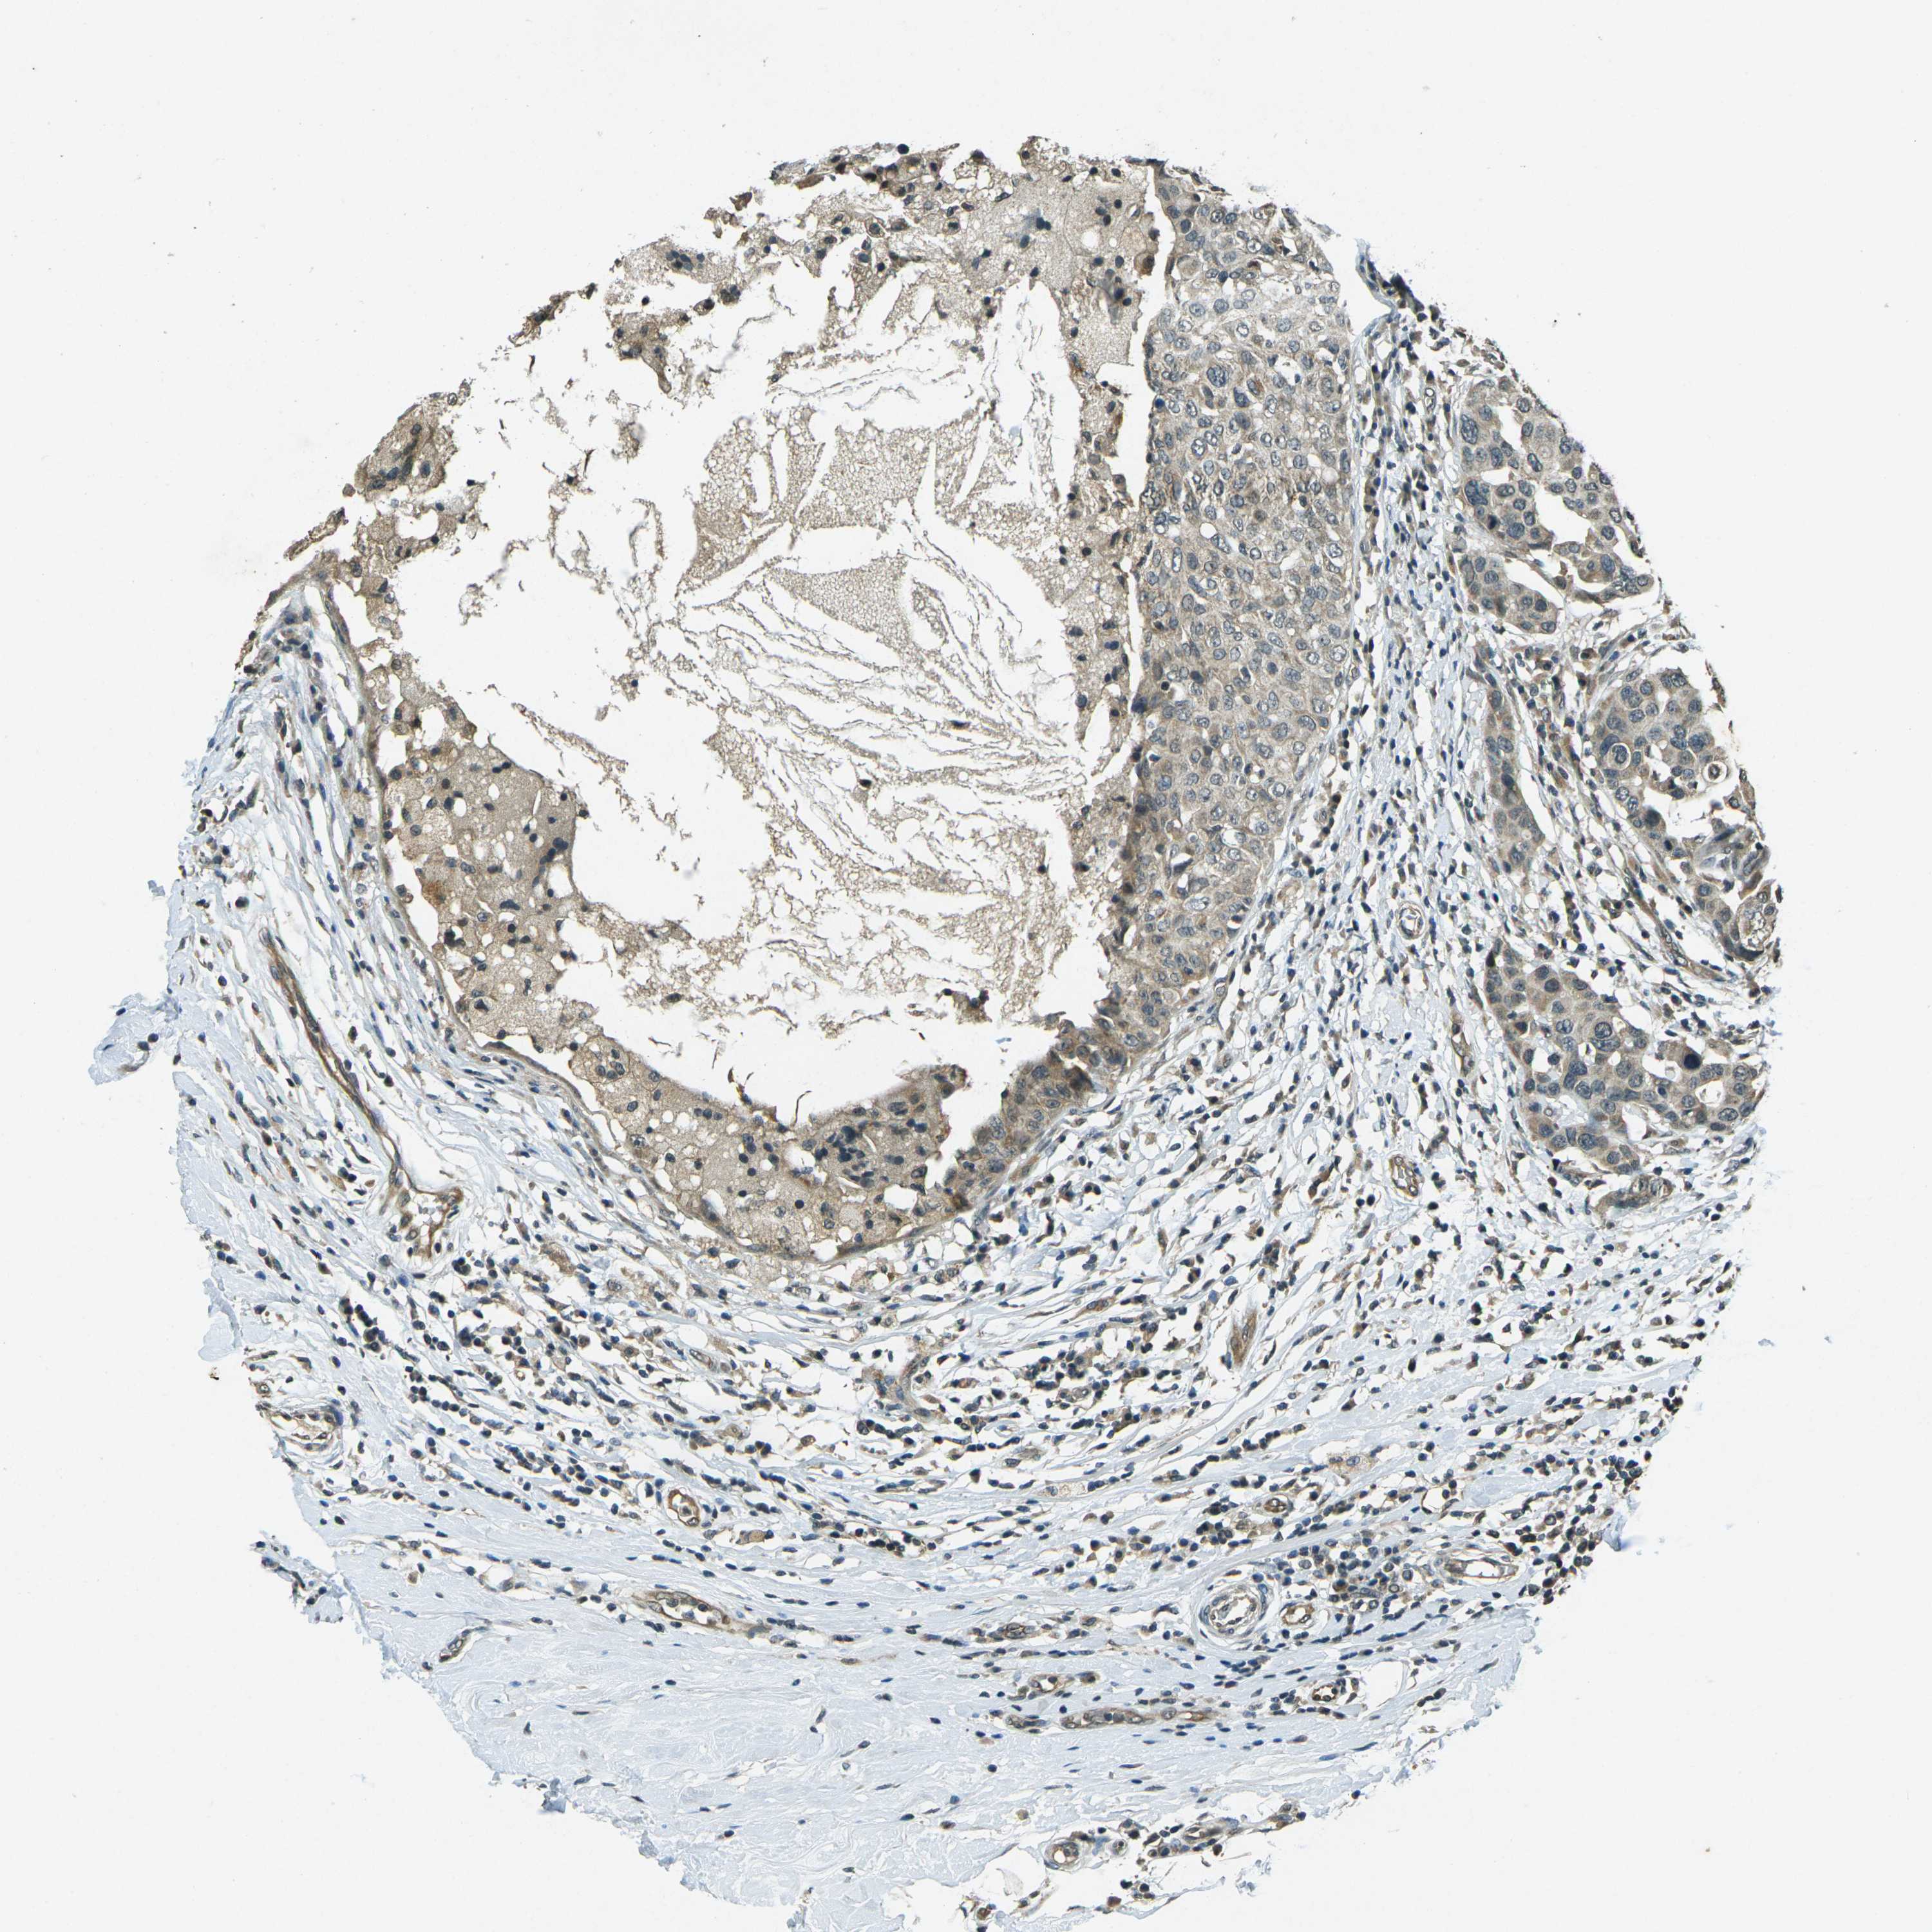

CANCER BREAST CANCER Show tissue menu

BRCA TCGA BRCA VALIDATION PROTEIN EXPRESSION

ANTIBODIES

AND

VALIDATION